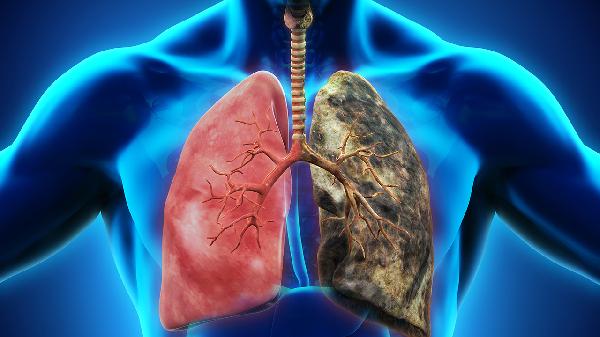

55岁,本该是享受天伦之乐的年纪,却被肺癌晚期打乱了所有计划。化疗一年后,身体像被掏空的容器,每天与疼痛为伴——这不是个例,而是许多癌症患者正在经历的困境。当现代医学手段开始力不从心时,我们还能做些什么来提升生存质量?